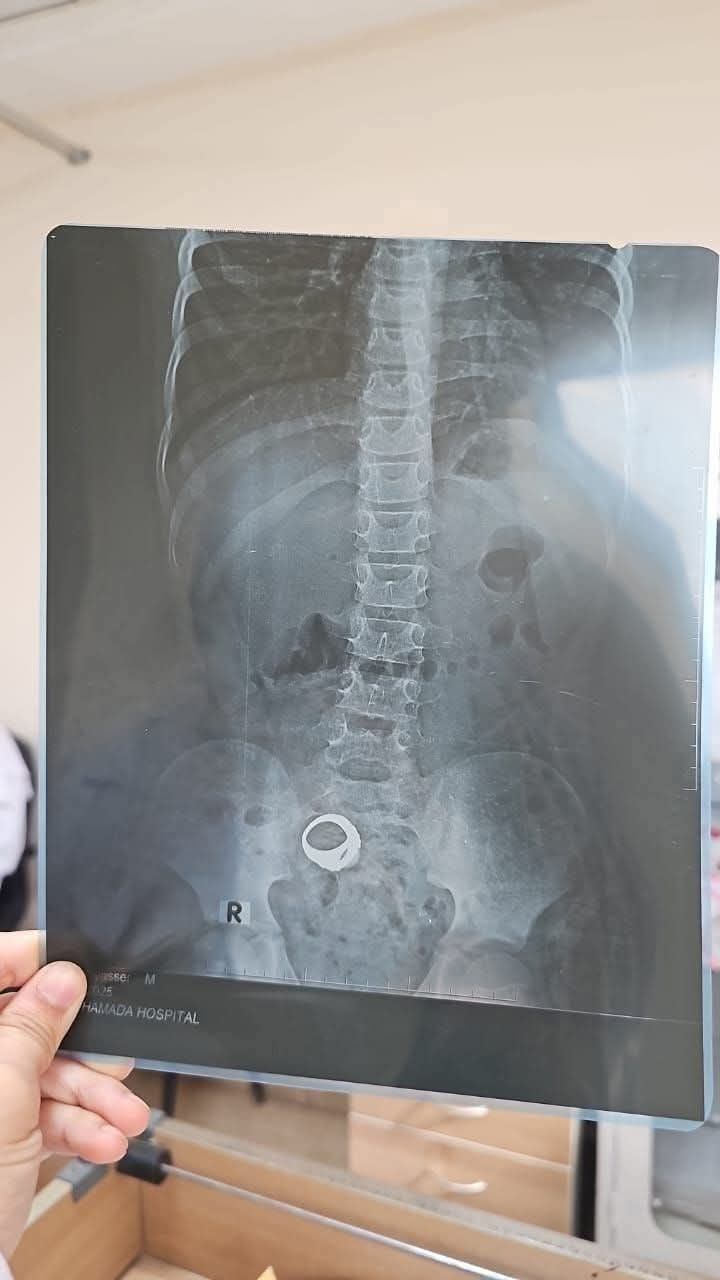

الخاتم المعندى يظهر فى الأشعة

شهدت مدينة كوم حمادة بمحافظة البحيرة حالة من الجدل، عقب انتشار دعوات تطالب والدة الطفل معاذ عمار بالعودة إلى المستشفى العام لمتابعة حالة طفلها، بعدما أظهرت الأشعة الطبية وجود جسم معدني داخل الأمعاء مما قد يؤدي إلى مخاطر صحية جسيمة.

وأكدت إدارة المستشفى أنه تم الكشف على الحالة، وأن والدة الطفل أجرت الأشعة اللازمة على منطقة البطن، لكنها غادرت قبل انتظار النتيجة، ولم تعد مرة أخرى للعيادة الخارجية لمتابعة الحالة الصحية للطفل.